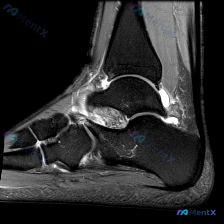

病例影像读片分享 今天整理了一例踝关节MRI的读片资料,把分析思路分享给大家一起讨论。 基本影像信息 这是一张踝关节矢状位T2加权MRI,可以清晰显示胫骨远端、距骨、跟骨、舟骨、楔骨等踝关节复合体骨性结构,T2序列对液体信号显示清晰。 核心阳性发现 1. 多关节广泛积液:胫距关节前后隐窝、距下关节间...